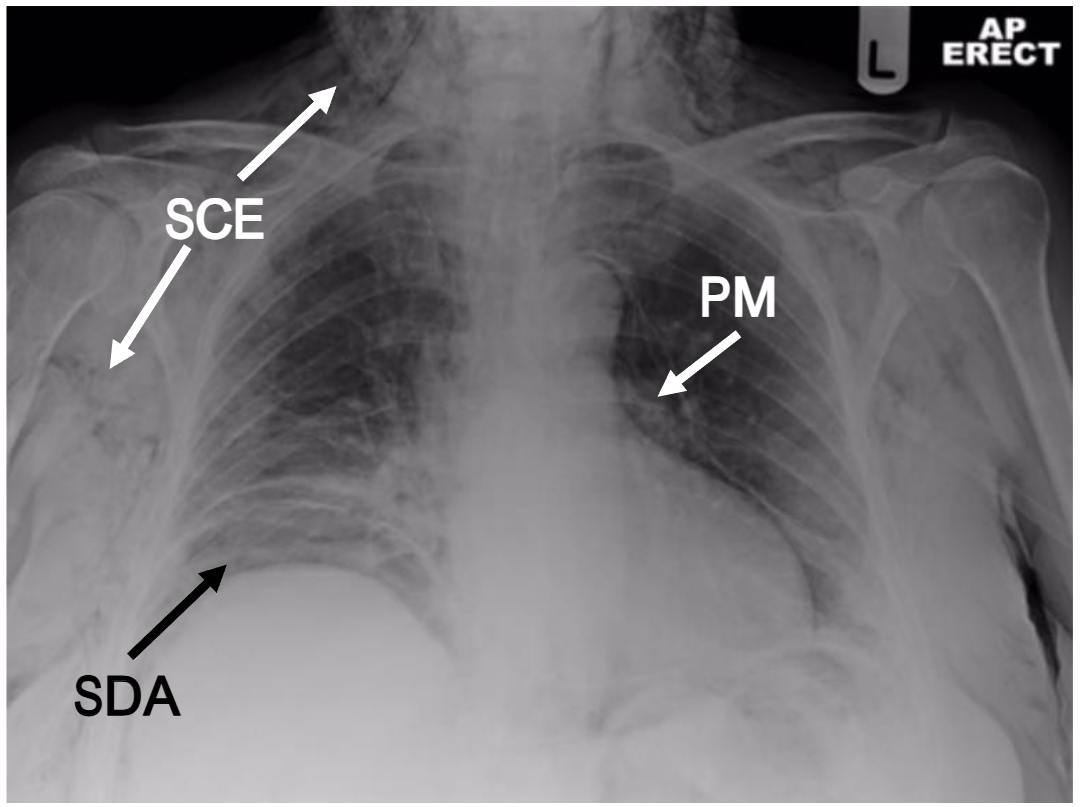

In most developed countries, there is less reliance on simple radiographs but an appropriately exposed radiograph can reveal subcutaneous emphysema clearly (see Figure 1) and may suggest a cause.

However, computed tomography (CT) is becoming a much more common early diagnostic tool as the rapidity, yield and specificity of radiological information is significantly greater. In the case of subcutaneous emphysema, CT imaging may reveal its anatomical site and extent, it may still be extremely challenging for the reporting radiologist to identify its origin in the absence of relevant clinical information or intra-abdominal stigmata. Indeed, subcutaneous emphysema of the head, neck and thorax may not even prompt the clinician to request inclusion of the abdomen. Occasionally, however, the information provided by an adequate CT scan is invaluable and can lead to a rapid diagnosis (see Figure 2). This review aims to encourage clinicians to include sub-diaphragmatic causes of acute subcutaneous emphysema within their differential diagnosis.